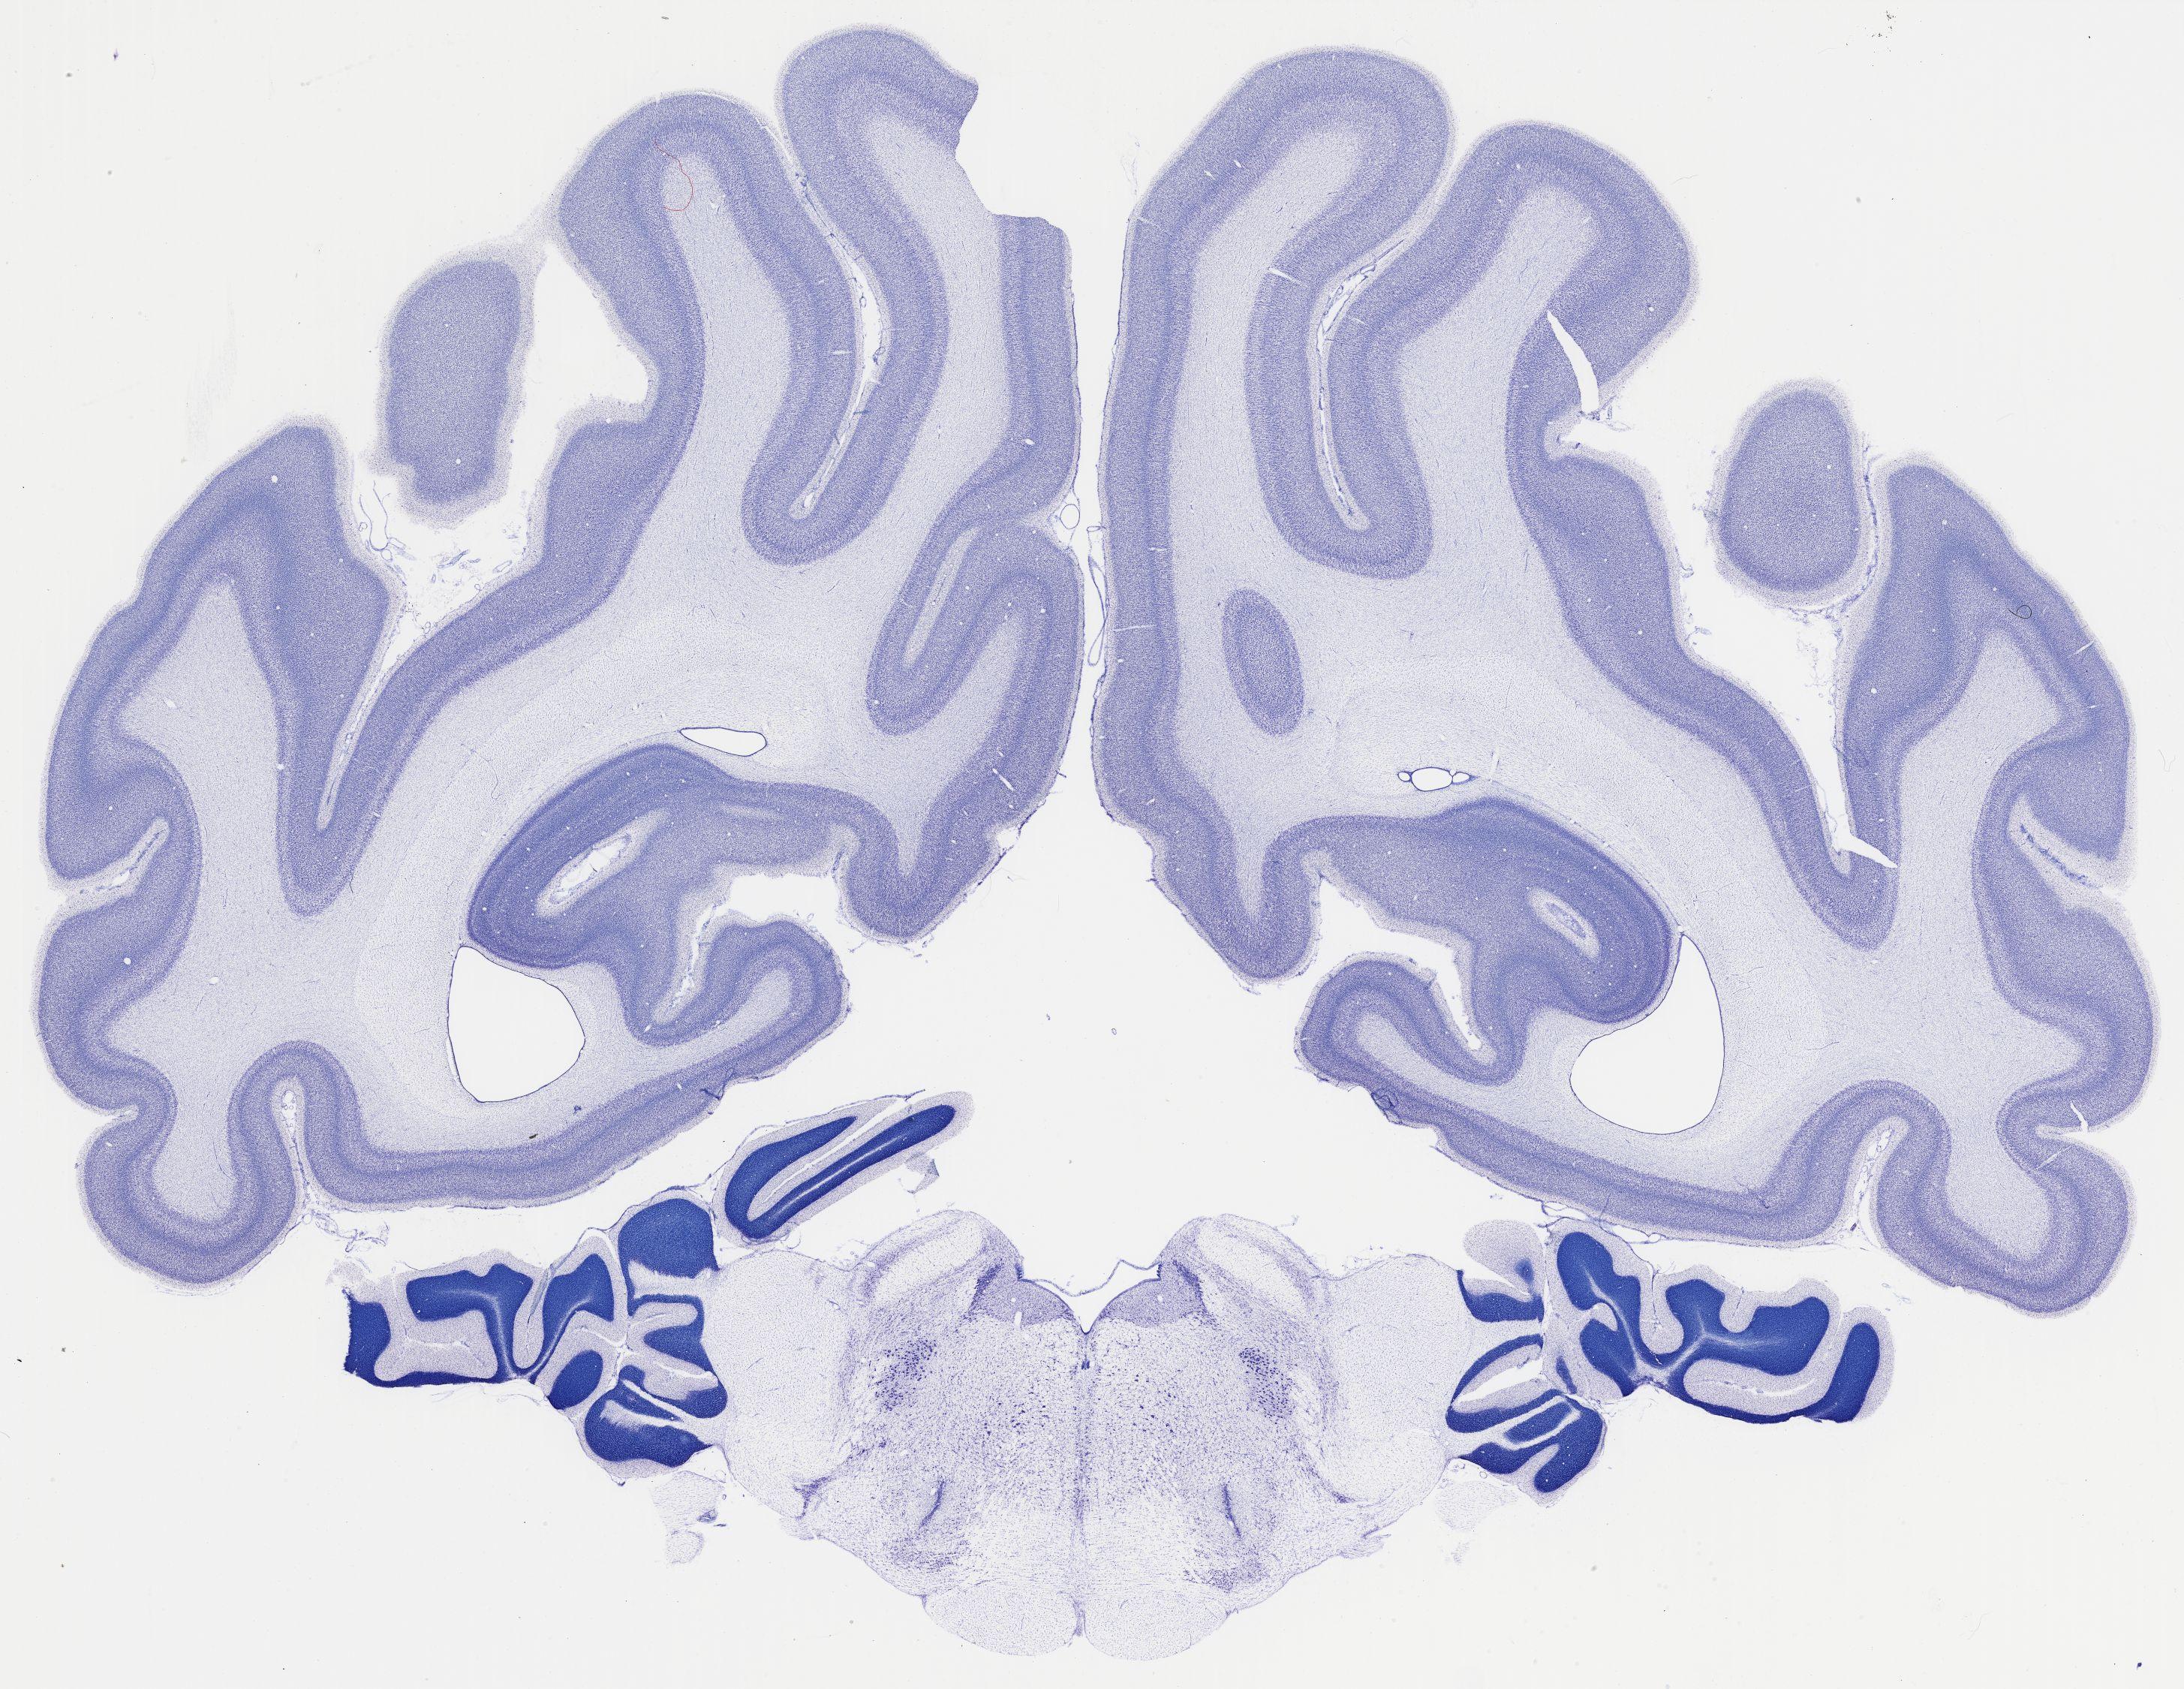

Datasets -> Chlorocebus Aethiops -> Nissl, coronal, histo, Whole-Brain, adult

[ Metadata ]   ·   Source: NeuroScience Associates

Displaying Sections 481 thru 520 of 740 Sections for this Dataset

thumbnail

523